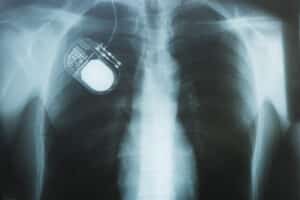

X-ray of a nerve stimulation device in a patient's chest to stimulate the vagus nerve and minimize painChronic pain can affect every part of daily life, from sleep and mood to work and mobility. For many people, especially those who have tried multiple treatments without success, lasting relief can feel out of reach. Vagus Nerve Stimulation offers new hope for those living with persistent pain.

Vagus Nerve Stimulation, or VNS, is a therapy that delivers mild electrical impulses to the vagus nerve, a key part of the nervous system that influences how the body processes pain. A small device is implanted under the skin in the chest and connected to the nerve in the neck. These impulses help disrupt pain signals traveling to the brain, offering relief to patients with certain chronic conditions.